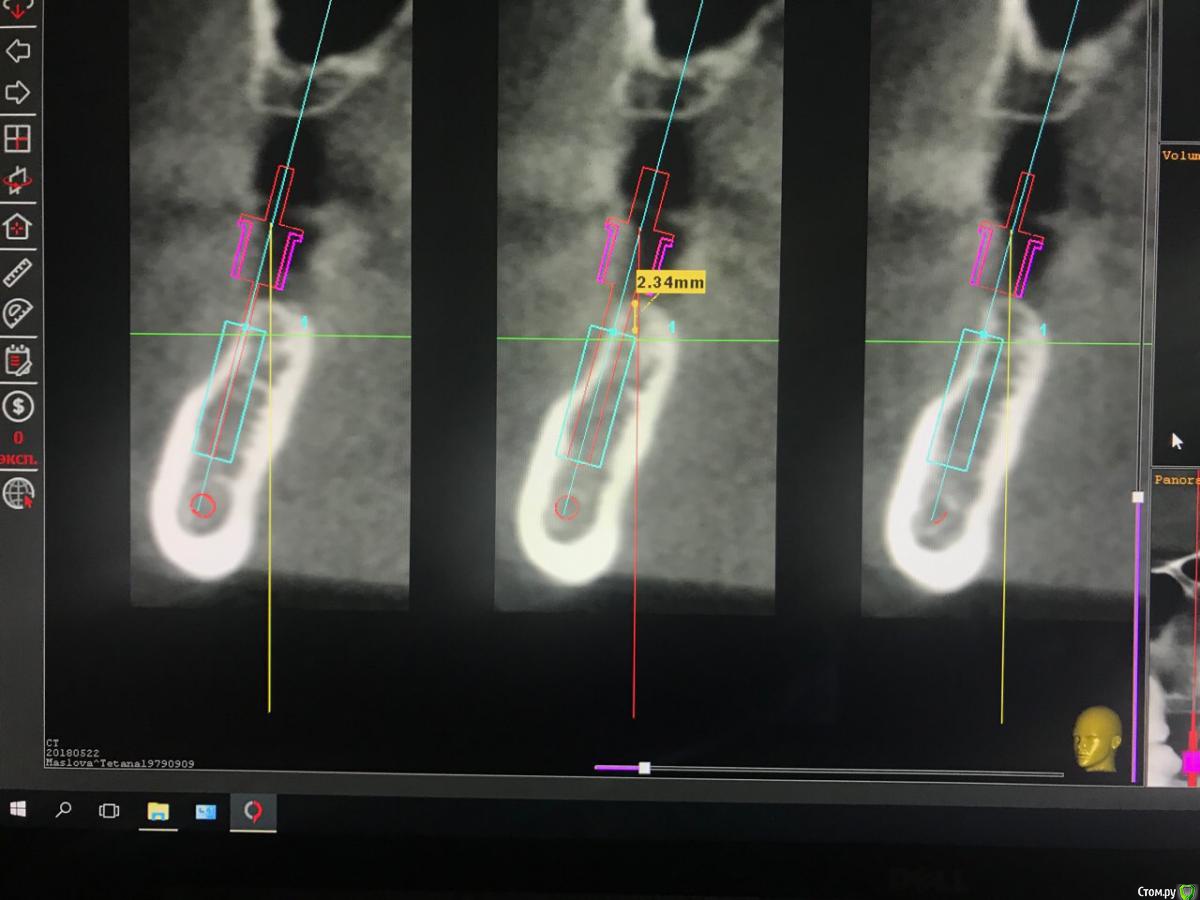

dr.Dre Опубликовано 27 мая, 2018 Поделиться Опубликовано 27 мая, 2018 Добрый вечер уважаемые коллеги ,посмотрите правильно ли расставлены мплантанты , пациентка 60 лет от 33 до 43 все будет удаляться, планирую поставить балку незнаю где поставить 4 импл.?Второй клинический случай можна ли поставить 12 мм имплант,а вестибулярную стенку засыпать графтом? Ссылка на комментарий

Evikrol Опубликовано 27 мая, 2018 Поделиться Опубликовано 27 мая, 2018 (изменено) Если хотите балку, можно смело ставить в лунки клыков и резцов, только я бы редукцию небольшую сделал костными кусачками, хотя бы на 5 мм, чтобы балка поместилась. Длинна 11,5 или 13 мм. Только внимательно изучите кт и запомните направление сверления, что бы не перфорировать вестибулярную стенку Лучше конечно всена4, но надо уметь работать с мультиюнитами Изменено 27 мая, 2018 пользователем Evikrol Ссылка на комментарий